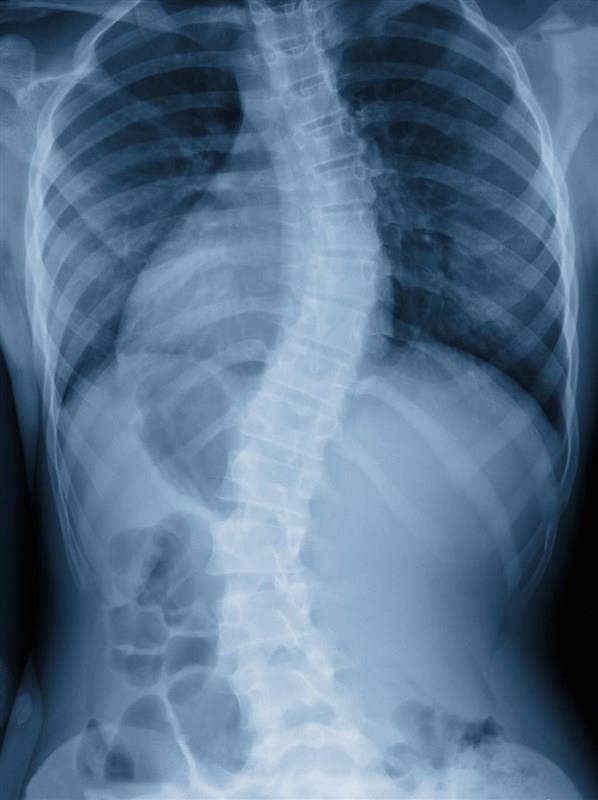

The spine has three natural curves; however, scoliosis is defined as the abnormal, lateral curvature of the spine. It can be disfiguring and painful if left untreated over an extended period of time. As the spine bends, the vertebrae can become twisted and pull the muscles and other bones (such as the ribs) around with them. Multiple curvatures can also occur with time to cause an S-shaped curve. In these cases, it may be hard to detect any abnormalities as the double curves can counteract one another, however, this can affect hip height and mobility.